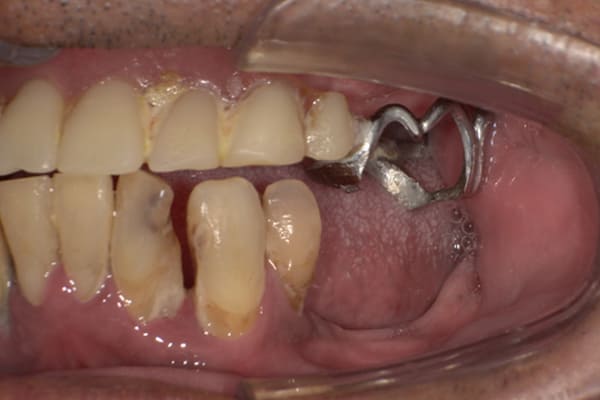

入れ歯が沈み込むことを防止するストッパーがない入れ歯を装着されていたため、お食事により入れ歯が沈み込みお痛みがでている状態でした。

笑った際に、太いバネが左右に見えるため、あまり大きく笑うことを避けていらっしゃいました。

作製した入れ歯は、お食事の際に入れ歯の沈み込みを予防するため、適切なストッパーを付与することで、入れ歯は沈み込まなくなり、お痛みは消失しました。

右下のバネの位置は後ろに、左下のバネは見えづらい形態のバネを用いる設計とすることで笑った際にバネが見えないようになり、気にされることはなくなられました。

裏側の見えない部分は金属を用いることで、お食事の際の入れ歯の動き、沈み込みを抑えお痛みがでづらく、入れ歯の動きが抑制されることで、長期的に残りの歯に負担のかかりにくい設計としました。